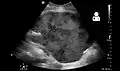

Imaging

Post operatively, kidneys are periodically assessed by ultrasound to assess for the imaging and physiologic changes that accompany transplant rejection. Imaging also allows evaluation of supportive structures such as the anastomosed transplant artery, vein, and ureter, to ensure they are stable in appearance.

- Postoperative bleeding following kidney transplant as seen on ultrasound[80]

Postoperative bleeding following kidney transplant as seen on ultrasound[80]